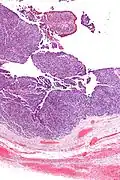

It is not related urothelial carcinoma.[1] It is in the transitional cell category of ovarian tumours which also includes malignant Brenner tumour and benign Brenner tumour.

Low mag. -